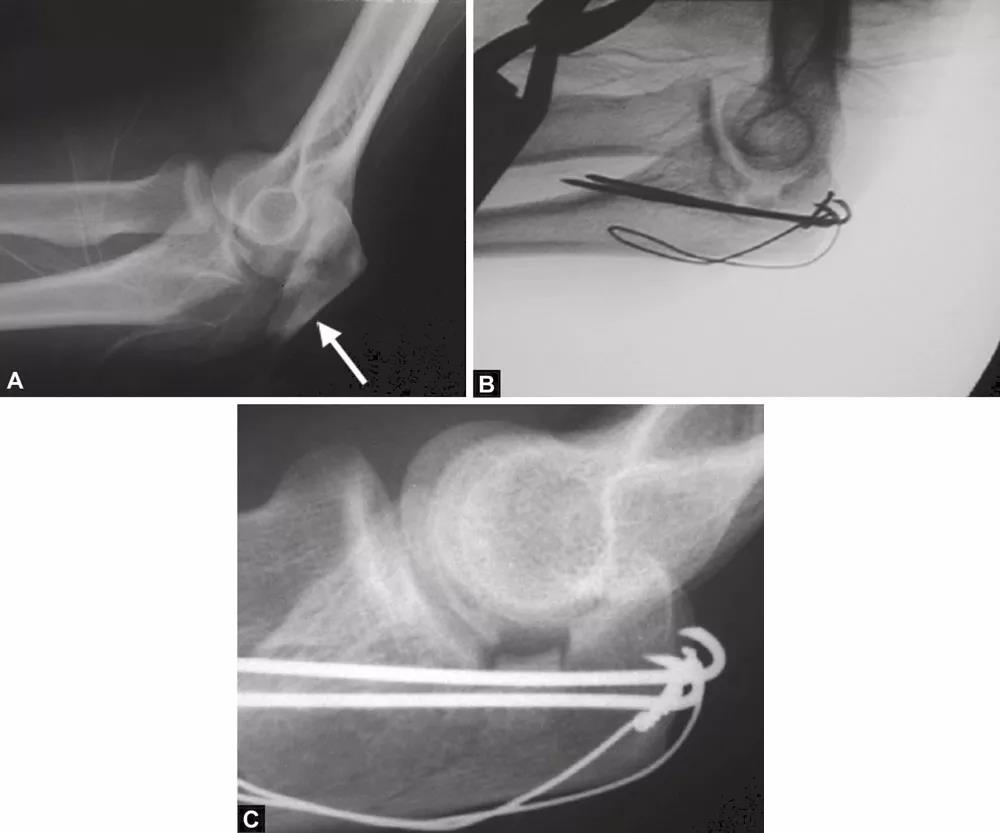

图1A~C(A)关节压缩骨折不易觉察,有经验的医生会注意到从冠状突到鹰嘴尖的关节间隙增宽而得出诊断;(B)如果没有的观察力,医生甚至会在术中X线片检查中都漏诊明显的压缩骨折。医生的注意力完全集中在检查植入物的位置上,因此容易忽略关节不一致;(C)术后摄片显示压缩骨折未复位

图3A~C关节压缩骨折在鹰嘴斜位片中完全隐匿。在箭头的部位变窄可能是一个提示。如果不知道这种可能性,医生就会忽略该手术X线片检查中明显的关节面压缩骨折。术后标准的侧位片良好地显示了关节面压缩骨折。该医生未能完成最初的手术目标